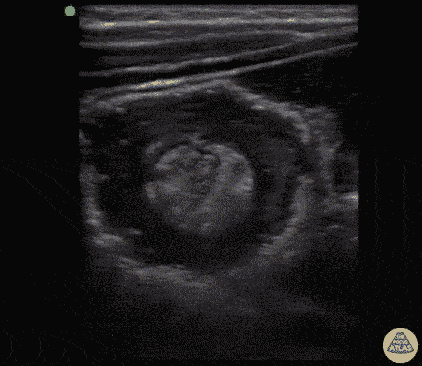

Peds-Gastrointestinal - Intussusception with Target Sign

4-year-old with colicky abdominal pain, vomiting once this AM, on exam abdomen soft and non-tender and pt well-appearing. POCUS performed demonstrating target sign. A hyperechoic fatty core can be seen within the intussuception inside hypoechoic edematous large bowel on both transverse and longitudinal views. Dr. Sathya Subramaniam, Pediatric EM Fellow - Kings County/SUNY Downstate